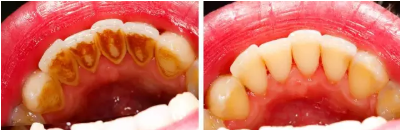

對大多數(shù)人來說,去醫(yī)院潔牙時,牙齒上的牙菌斑基本上已經(jīng)發(fā)展成了牙結(jié)石。牙結(jié)石最容易沉積的部位就是下前牙的舌側(cè)和上后牙的頰側(cè)。定期潔牙的人也會有不同程度的牙結(jié)石堆積,間隔的時間越長,堆積的牙結(jié)石就會越厚越大。

牙結(jié)石首先在牙齒與牙齦的交界處開始沉積,如果堆積的牙結(jié)石沒有及時去除,面積就會越來越大,并朝著牙齦下發(fā)展,導(dǎo)致牙齦炎癥。牙齦炎癥會引起牙齦腫痛,這種腫痛感就像皮膚被針刺一樣。

當(dāng)牙齦下存在牙結(jié)石,或有牙槽骨吸收跡象時,常規(guī)潔牙往往無法清除牙齦下的結(jié)石,此時需要進(jìn)行牙周刮治了。